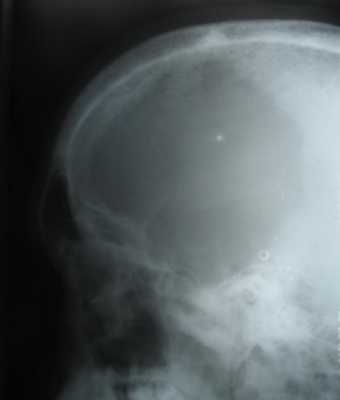

При поражении костей черепа иногда бывает увеличена окружность головы, при постукивании по черепу отмечается тимпанический звук «спелого арбуза». При рентгенологическом исследовании скелета можно обнаружить генерализованный остеопороз или гигантоклеточные опухоли. К поздним проявлениям следует отнести эпулиды и другие мягкотканные опухоли десен и нижней челюсти, шатание или выпадение зубов, выпячивание челюсти и отсутствие твердой зубной пластинки.

Клиническая картина. Боли и припухание в поражённых костях; мышечная слабость; патологические переломы; полидипсия, полиурия; иногда в течение многих лет протекает незаметно для больного. Рентгенологически отмечают распространенный остеопороз, расширение костномозгового канала длинных костей, субпериостальная деминерализация; пятнистый рисунок костей черепа, субпериостальная резорбции дистальных отделов ногтевых фаланг. Лабораторно обнаруживают повышение содержания в крови кальция, щелочной фосфатазы, паратгормона, снижение показателей фосфатов.